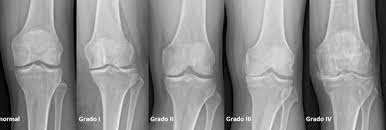

Terapia de ejercicio de dosis alta versus dosis baja para la osteoartritis de rodilla

Los resultados de este ensayo multicéntrico controlado aleatoriono respaldan la superioridad del ejercicio en dosis altas sobre el ejercicio en dosis bajas para la mayoría de los resultados. Sin embargo, se encontraron pequeños beneficios con altas dosis de ejercicio para la función de la rodilla en deportes y recreación y para la calidad de vida. Ann Intern Med, 24 de enero de 2023

Antidepresivos para la artrosis de cadera y rodilla

Hay evidencia de certeza alta de que el uso de antidepresivos para la artrosis de rodilla produce una mejoría insignificante desde el punto de vista clínico en el dolor medio y la funcionalidad. Sin embargo, un pequeño número de personas tendrá una mejoría importante del 50% o más en el dolor y la funcionalidad. Este hallazgo fue consistente en todos los ensayos. El dolor en la artrosis se podría deber a diversas causas que difieren entre las personas. Es posible que la causa del dolor que responde a este tratamiento solo esté presente en un pequeño número de personas. Hay evidencia de certeza moderada de que los antidepresivos tienen un pequeño efecto positivo sobre la calidad de vida, con heterogeneidad entre los ensayos. Cochrane Database of Systematic Reviews 21 de octubre de 2022

Artrosis de rodilla: eficacia y seguridad de la viscosuplementación

Existe evidencia concluyente de que la viscosuplementación conduce a una pequeña reducción en el dolor de la osteoartritis de rodilla en comparación con el placebo, que resulta menor a la diferencia mínima clínicamente importante. También hay evidencia concluyente de que la intervención se asocia con un riesgo aumentado de eventos adversos graves, por lo que se considera que estos hallazgos no respaldan su uso generalizado en el tratamiento de la artrosis de rodilla. British Medical Journal, 6 de julio de 2022.